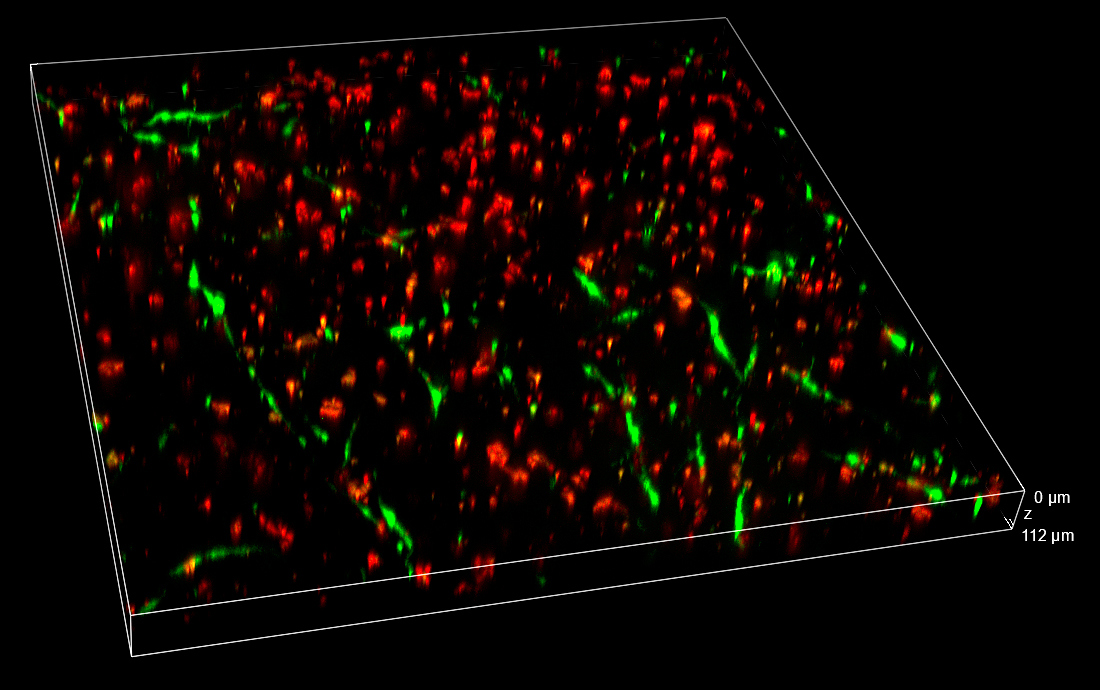

In the Figure 2, the full field of view (FOV) in XYZ dimensions collected 24 h post-treatment is shown. Thanks to the 25 mm diagonal FOV of the camera and to the ability to penetrate inside the sample without losing the spinning disk confocality, it was possible to visualize and record cells that homogeneously colonize the entire thickness of the 3D matrix.

Figure 2. 3D view of the entire FOV acquired with spinning disk at 24 h post-treatment. FOV with XY=4422×4422 µm, Z=530 µm. 3D matrix thickness was entirely acquired. Tumor target A673 cells are shown in red and AD-MSCs TRAIL in green.

Data obtained from live monitoring of co-cultures in VITVO were compared with end-point readouts from fixed samples at specific time points post-treatment (24 and 72 h, Figure 8). 3D comparison among three different FOVs confirmed a homogeneous distribution of cells without any significant inter-field difference. These data point out that AD-MSCs TRAIL were persisted over time, instead of A673 tumor cells which massively decreased in their signal and cell density (Figure 8).

Figure 8. Z-stacks on VITVO FOVs collected and fixed at different time points with spinning disk. 3 different FOVs corresponding to 24 h and 72 h post-treatment fixed sample, respectively (10x objective magnification).